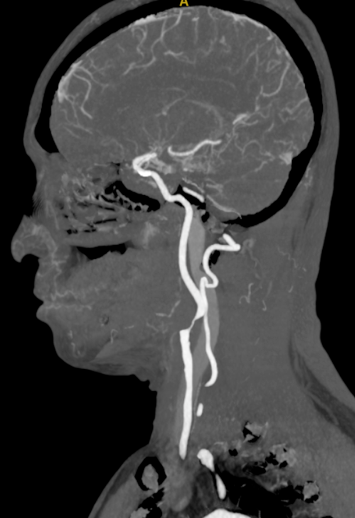

头颈部CTA

波科支架怎么样径技-弓上病例大赏|第205期·放疗后症状性颈动脉狭窄支架置入治疗一例_https://www.jmylbn.com_新闻资讯_第9张

波科支架怎么样径技-弓上病例大赏|第205期·放疗后症状性颈动脉狭窄支架置入治疗一例_https://www.jmylbn.com_新闻资讯_第10张

波科支架怎么样径技-弓上病例大赏|第205期·放疗后症状性颈动脉狭窄支架置入治疗一例_https://www.jmylbn.com_新闻资讯_第11张